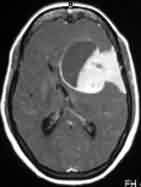

|

Bifalcine

meningioma-MRI

|

Falx meningioma-MRI

|

|

|

|

|

Convexity meningioma

with hyperostosis- MRI

|

Convexity meningioma

with hyperostosis- X-ray

|

|

|

|

|

Orbital meningioma-CT

|

Parasagittal

meningioma-MRI

|

|

|

|

|

Meningioma with

Associated pituitary adenoma-MRI

|

Olfactory groove

meningioma-MRI

|

|

|

|

|

Petrous

meningioma-MRI

|

Suprasellar

meningioma-MRI

|

|

|

|

|

Tuberculum sella

meningioma-CT

|

Diaphragm sella

meningioma-MRI

|

|

|

|

|

Meningioma with skull

infiltration-MRI

|

Intradiploic

meningioma-MRI

|

|

|

|

|

Sp. Wing en plaque

meningioma-MRI

|

Meningioma extending

through foramen ovale -MRI

|

|

|

|

|

Intraventricular

meningioma-MRI

|

Cystic meningioma

with dural tail-MRI

|

|

|

|

|

Tentorial

meningioma-MRI

|

Torcular

meningioma-MRI

|

|

|

|

|

Hemangiopericytoma-MRI

|

Jugular foramen

meningioma-MRI

|

|

|

|

|

F.M

meningioma-pre op-MRI

|

Multiple

Meningiomas -MRI

|